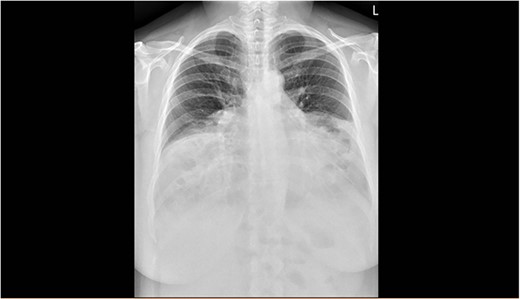

The spirometry results from her General Practitioner showed a restrictive pattern with FVC of 2.08L (55% predicted), FEV1 of 1.62L (54% predicted) and FEV1/FVC ratio of 0.78 (96% predicted). Her chest X-ray demonstrated a large hiatus or congenital hernia (Fig. 1). Subsequent computed tomography (CT) of the chest, abdomen and pelvis showed a large 88 × 48-mm defect of the anterior diaphragm consistent with MH. Hernial contents extended to the superior mediastinum and were primarily large bowel and omentum, with no intestinal obstruction (Figs 2–4).

Arterial contrast CT of the chest. Axial slice at the T4/5 level showing herniation of large bowel, small bowel and omentum into the chest cavity. The defect in the anterior diaphragm measures 88.2 mm × 48.2 mm. Of note is the significant reduction in the size of the lung fields.